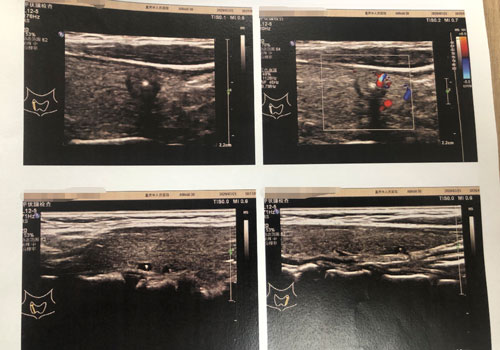

夏女士的甲状腺影像检查。院方供图

张帆主任告诉我们:“患者有严重的肾脏疾病和肾性高血压,手术风险比正常人大很多。手术的打击可能会使肾衰加重,术后出现高钾血症等电解质紊乱,这些都是很危险的。”